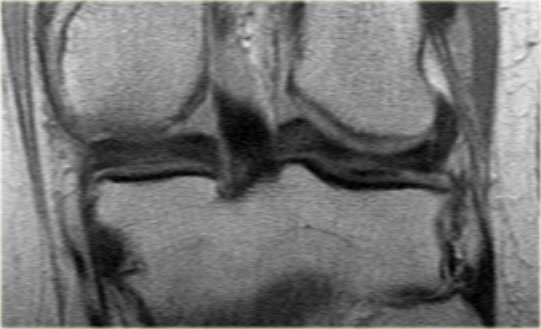

Rách kiểu quai xách là loại rách dọc theo chiều đứng có kèm di lệch.

Mảnh bờ trong bị di lệch có hình dạng giống như quai của một chiếc xô.

Phần ngoại vi còn lại của sụn chêm, phần lớn hơn, có hình dạng giống như thân chiếc xô.

Loại rách này chiếm khoảng 10% trong tổng số các trường hợp rách sụn chêm.

Dấu hiệu PCL đôi

Dấu hiệu dây chằng chéo sau (PCL) đôi là một dải giảm tín hiệu nằm song song và ở phía trước-dưới so với PCL trên ảnh MRI mặt phẳng đứng dọc.

Đây là dấu hiệu có độ đặc hiệu cao trong chẩn đoán rách sụn chêm kiểu quai xô (3).